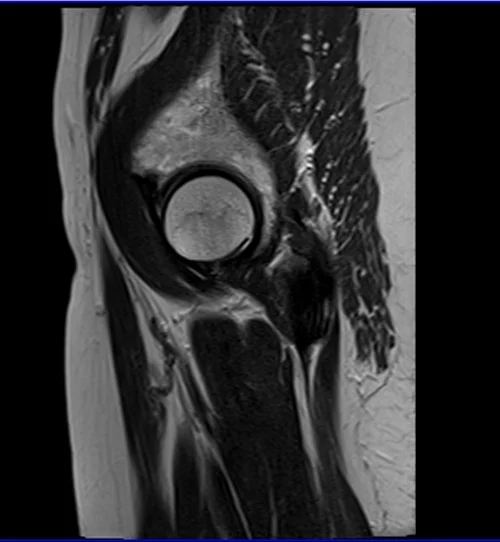

mri hips sag t2 image 3 - MRI